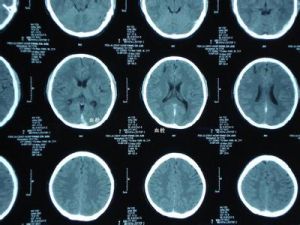

腦靜脈竇血栓(cerebral venous sinus thrombosis,CVST)是一種特殊類型的腦血管疾病,發生率不足所有卒中的1%。通常以兒童和青壯年多見,而兒童患者中又以感染引起的側竇和海綿竇多見。化膿性中耳炎和乳突炎患者易並發橫竇(transverse portion of lateral sinus)和乙狀竇(sigmoid portion of lateral sinus)的血栓形成,統稱為側竇血栓形成(lateral sinus thrombosis)。

根據病變性質,CVST可分為炎症型和非炎症型兩類。炎症型中海綿竇和橫竇是最常受累的部位;而非炎症型中上矢狀竇最容易受累。橫竇乙狀竇血栓形成多繼發於化膿性乳突炎或中耳炎。

為了更好地理解CVST的臨床症狀和體徵,首先應該區分兩種不同的病理生理機制。即腦靜脈血栓——由靜脈梗阻所產生的局灶性症狀;腦靜脈竇血栓——由靜脈竇血栓導致顱內高壓。在大多數患者中,這兩種病理生理過程常同時存在。腦靜脈的閉塞產生局部腦水腫和靜脈型梗死。病理檢查可發現擴大、腫脹的靜脈,水腫(包括細胞毒性水腫和血管源性水腫),缺血性神經元損害和點狀出血。而後者可融合成大的血腫被CT檢測到。橫竇乙狀竇血栓形成可導致靜脈壓升高,從而影響了腦脊液的吸收而產生顱內高壓。因為影響的是腦脊液循環的最後通路,蛛網膜下腔和腦室之間沒有壓力梯度,所以腦室並不擴張,也不會導致所有的患者都出現腦積水。